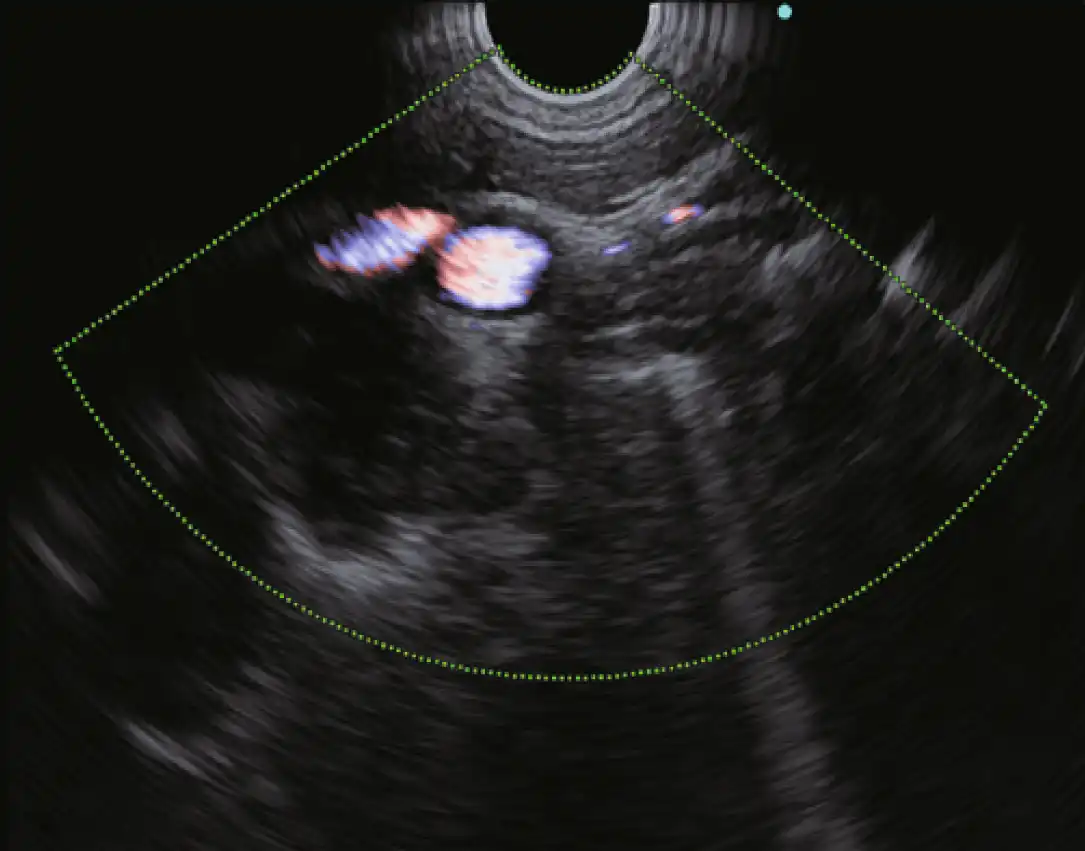

多普勒模式

EU-ME3 提供三种基本的多普勒模式,以更清楚地分辨血流--彩色血流、能量血流和脉冲波多普勒(PWD)。多普勒模式可用于支持更安全的手术,使病人和医生都受益。

除了三种基本的多普勒模式外,EU-ME3还具有H-Flow模式。H-Flow是一种更敏感的多普勒模式,可显示定向血流,且花纹较少。它对回声内窥镜尖端周围的小血管成像特别有用。

彩色流 能量流

脉冲波多普勒 H-Flow